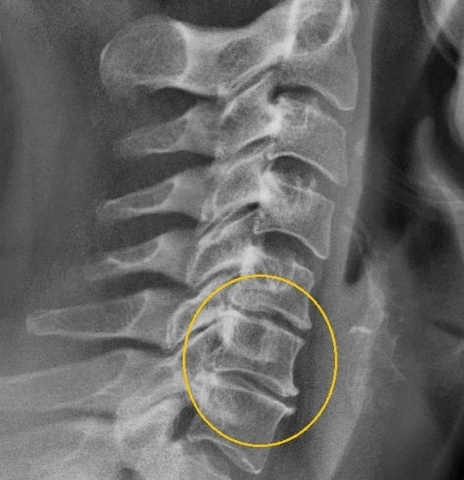

II etapp

Selles etapis algas selgroogsete väljaulatuvus, lülisamba praod kitsad, kollageeni ketta kiu kiud hävitatakse. Närvipurude kokkusurumise tõttu on punkt -loodusel märgatavaid valulikke sümptomeid, mis intensiivistuvad kaela ja pea pöörde liikumise ajal. Siin saate juba kahtlustada emakakaela osteokondroosi, mille sümptomid teises etapis on järgmised:

III etapp

Ketta kiuline rõngas hävitatakse, moodustatakse hernias. Kolmandas etapis on nende nõrga fikseerimise tõttu selgroogu deformatsioon, nihe ja nihed. Sümptomid on järgmised: